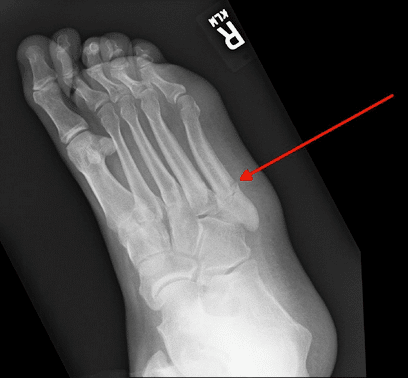

1. What is a Jones fracture?

A Jones fracture is an injury to the base of the little toe, also known as the fifth metatarsal.

In most cases, a Jones fracture is caused by a twisting injury to your foot, such as landing on it wrong while coming down from a catch. Other causes include overuse, repetitive stress, and trauma.

Symptoms usually include pain on the outside of the foot, swelling, bruising, and pain with walking.